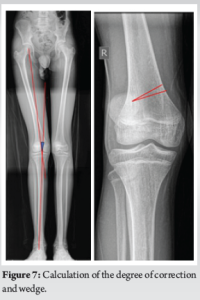

An anteromedial incision was made on the knee. The vastus medialis was retracted, and the osteotomy site was marked. The wedge to be taken and the degree of correction required was calculated previously based on X-rays based on geometric triangle method (Fig. 7). A 7 mm wedge was taken from the femur and the osteotomy site closed and fixed using a femoral osteotomy plate (Fig. 8). Following this, through a lateral parapatellar approach was taken for the trochleoplasty. The cartilage was sharply incised and elevated. Cancellous bone was removed using a 5 mm drill, preserving the subchondral bone stock (Trochlea Guide system – Arthrex, USA). The articular flap was then fixed to the underlying bone surface using 3 pushlock anchors and Vicryl tapes (Fig. 9). After this, the MPFL was reconstructed using a gracilis graft, fixed with 2 tunnels on the patella and to Schottle’s point on the femur.